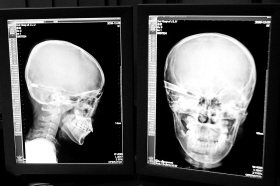

在接受x光檢查的小沖

“還是先做個X光透視,看一下箭桿到底有多深。”眼科醫生緊急趕到CT室查看,和放射科的幾位醫生共同研究后,決定先讓小沖做X光透視。

“如果再用點力,就從后腦穿出來了!”由于小沖無法移動,醫生拿來移動插座,將透視的光板放在小沖的移動病床上,透視后讓在場的醫生都吃了一驚:箭桿直接穿過了大腦和小腦,箭尖兒直抵后顱骨,足足有10余厘米。